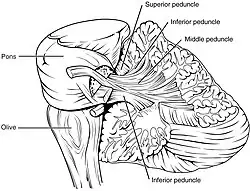

Coronal section of the cerebellum. Arbor vitae and cerebellar peduncles.

Arbor vitae and cerebellar peduncles.